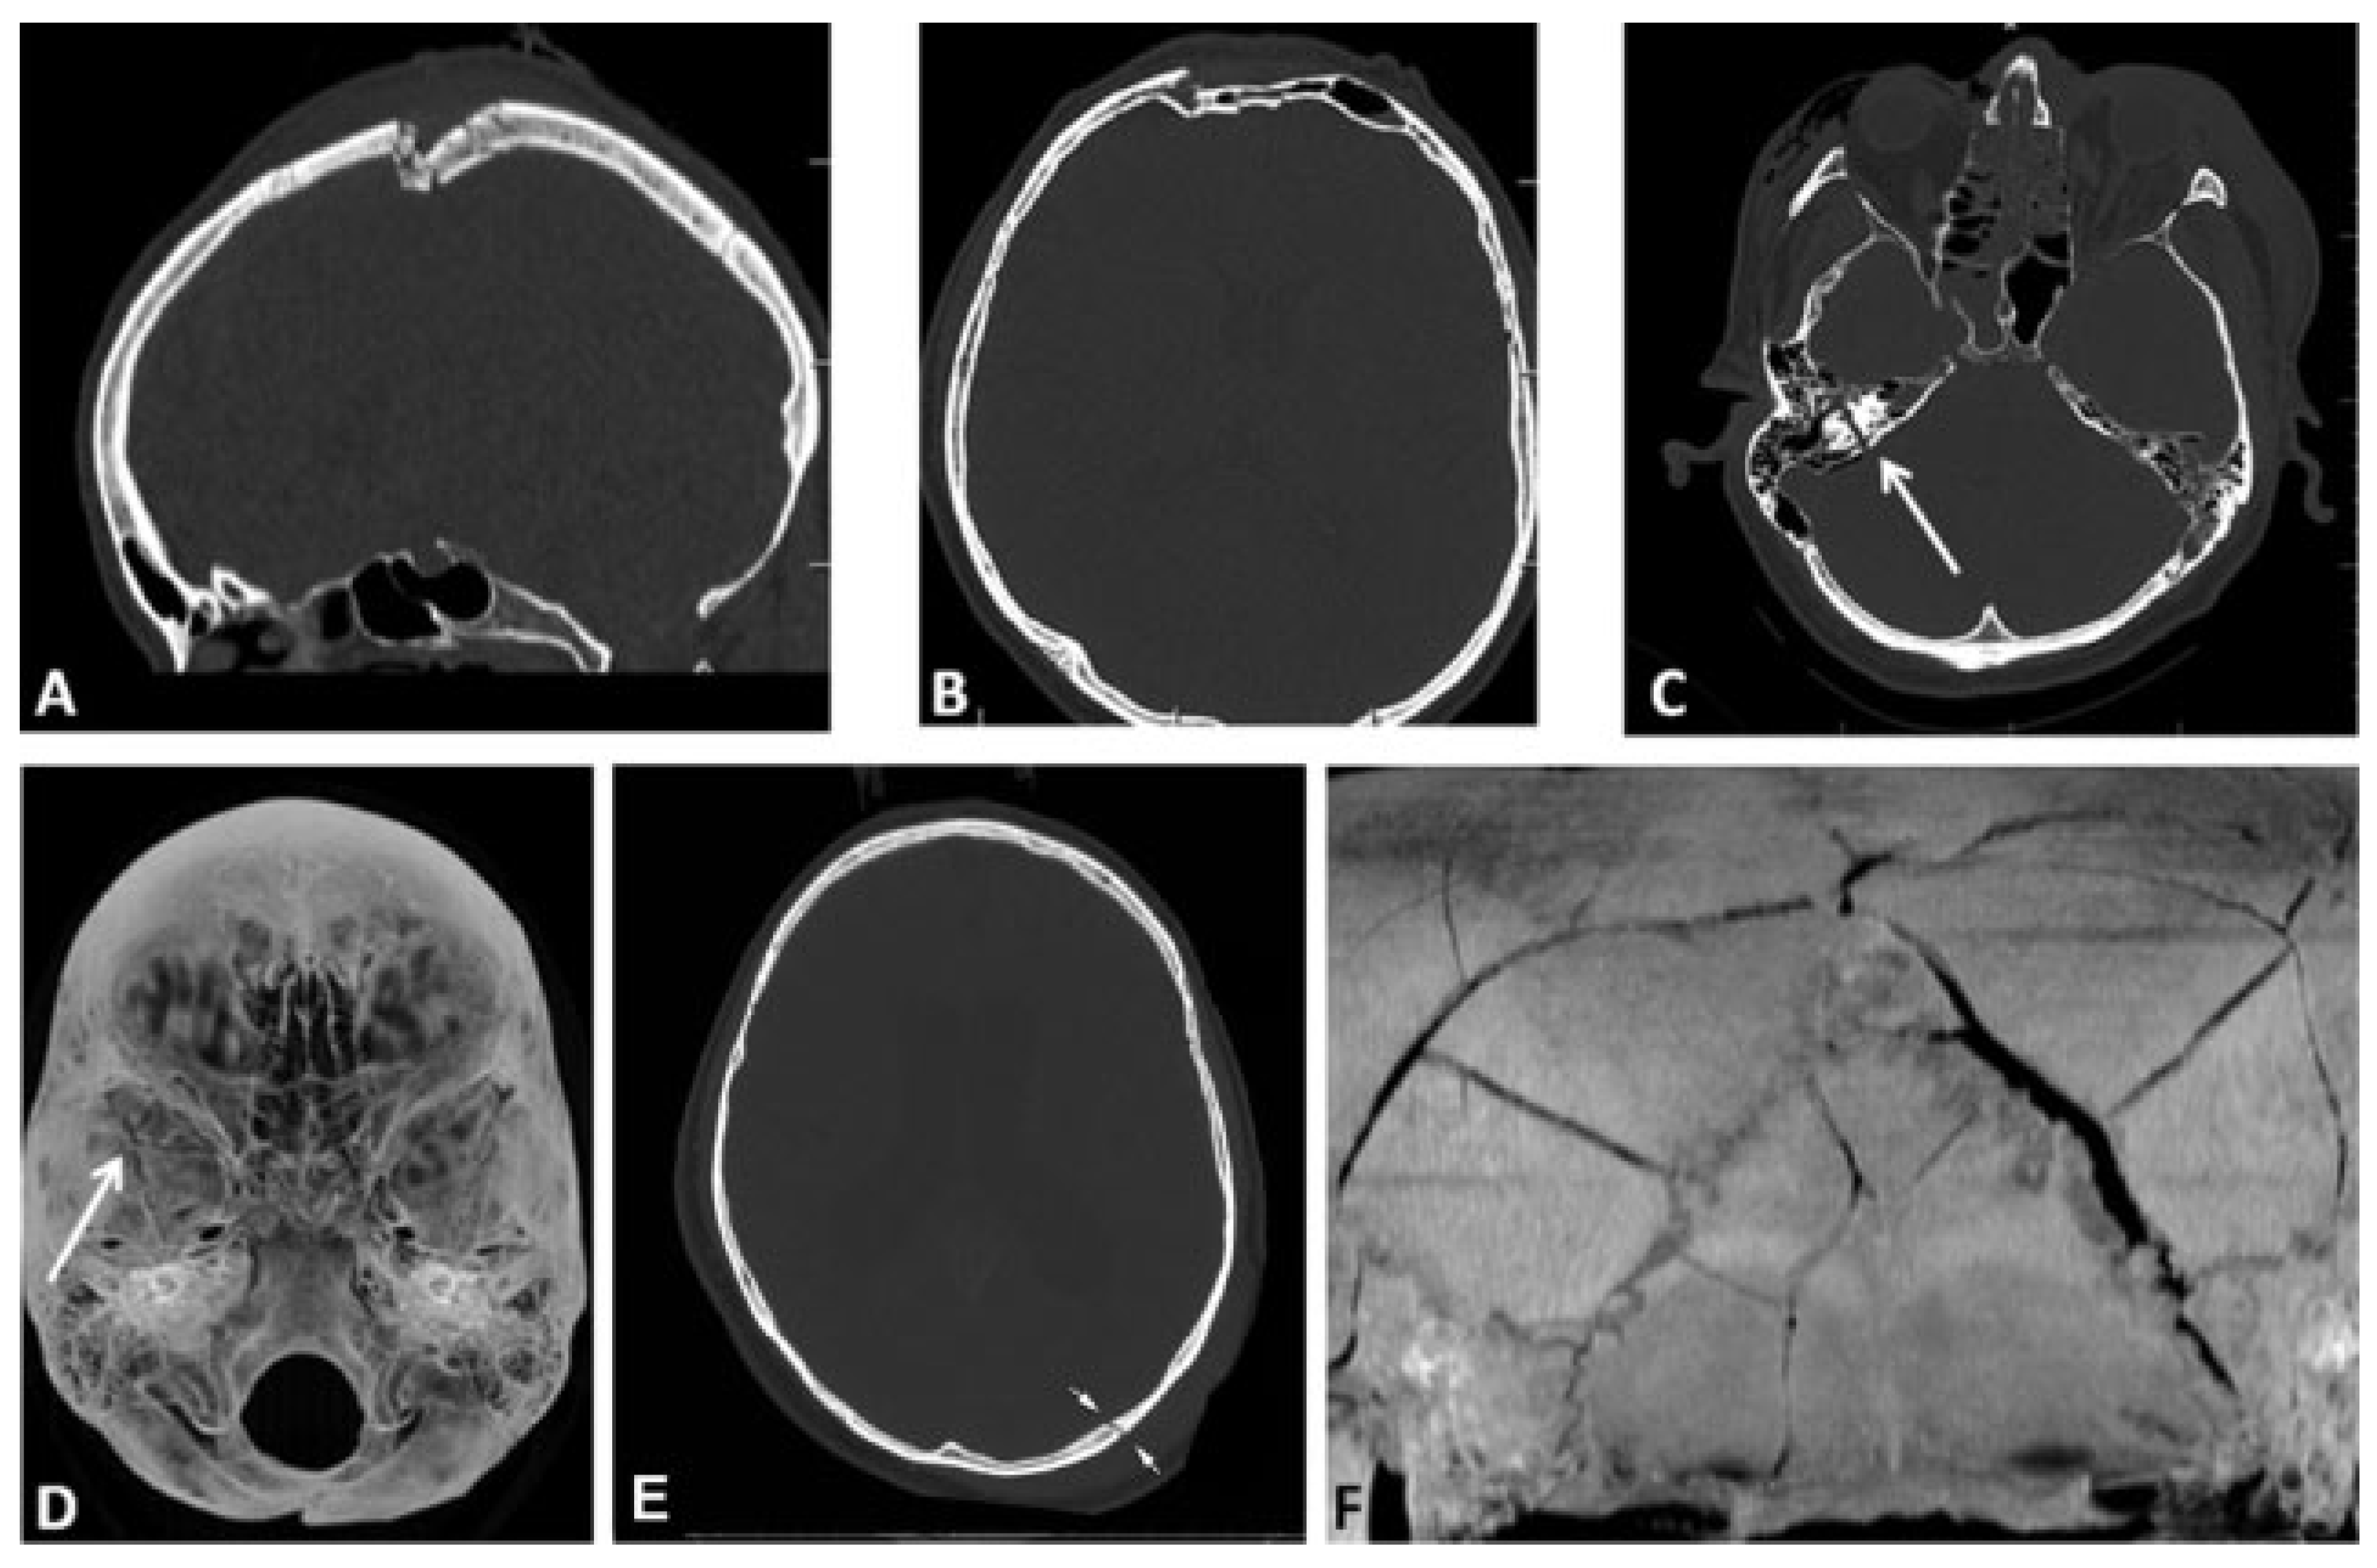

Associated Intracranial Features

A list of clinically relevant intracranial features that may be associated with skull base and/or cranial vault fractures is proposed in addition to the fracture classification system to support the diagnosis and decision process (Table 2). These features include the presence of intracranial air (0 = none, 1 = single, or multiple air bubbles [up to 3 mm diameter], 2 = pneumocephalus [larger air pockets > 3mm]) (Figure 4B–D), intracranial mass lesion (epidural, subdural, subarachnoid, intraventricular, and/or intraparenchymal hematoma, brain contusions, foreign bodies) (Figure 4E–H), as well as radiological or clinical evidence of dural rupture, with following cerebrospinal fluid (CSF) leak.

Figure 4. Examples of associated diagnostic features with skull base and cranial vault fractures. (A) Partial opacification in the sphenoid sinus with air–fluid level in computed tomographic imaging (representing possible the presence of blood or fluid). (B–D) Presence of intracranial air: single or multiple air-bubbles in the subdural spaces (arrows in B) or in the subarachnoid space (arrow in C); (D) pneumocephalus. (E–H) Intracranial mass lesions: (E) epidural hematoma in the left occipital region (arrowheads) with small mixed (epidural and subdural) hematoma in the right temporal region (arrows), (F) subdural hematoma of the right hemisphere (arrows) with extension along the falx (arrowhead), (G) intraventricular haematoma, (H) brain contusions.